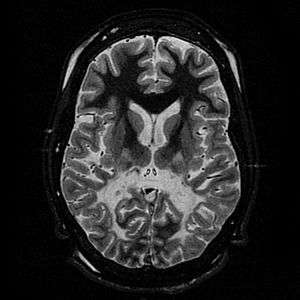

White matter, with reduced volume and increased signal intensity. The anterior white matter is spared. Features are consistent with X-linked adrenoleukodystrophy. | |

The Loes score is a rating of the severity of abnormalities in the brain found on MRI. It ranges from 0 to 34, based on a point system derived from the location and extent of disease and the presence of atrophy in the brain, either localized to specific points or generally throughout the brain. A Loes score of 0.5 or less is classified as normal, while a Loes score of 14 or greater is considered severe. It was developed by neuroradiologist Daniel J. Loes MD and is an important tool in assessing disease progression and the effectiveness of therapy.[12]